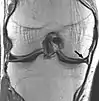

| Proton density weighted | PD | Long TR (to reduce T1) and short TE (to minimize T2).[7] | Joint disease and injury.[8]

|

![]() | |

Proton density

Proton density (PD)- weighted images are created by having a long repetition time (TR) and a short echo time (TE).[36] On images of the brain, this sequence has a more pronounced distinction between gray matter (bright) and white matter (darker gray), but with little contrast between brain and CSF.[36] It is very useful for the detection of joint disease and injury.[37]